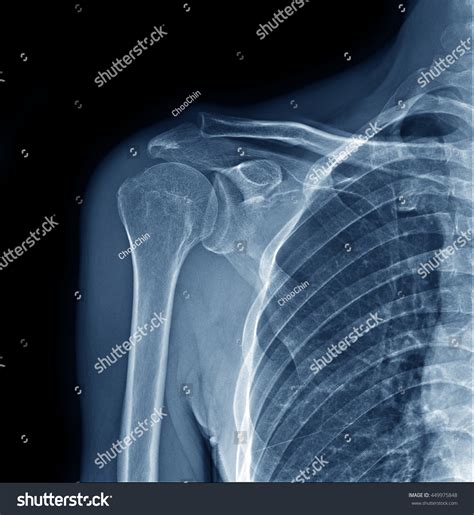

Understanding the intricacies of the X Ray Shoulder Joint is crucial for both medical professionals and patients alike. The shoulder joint is one of the most complex and mobile joints in the human body, making it susceptible to a variety of injuries and conditions. An X-ray of the shoulder joint provides valuable insights into the structure and health of this critical area, aiding in accurate diagnosis and effective treatment.

The shoulder joint is a ball-and-socket joint composed of three main bones: the humerus (upper arm bone), the scapula (shoulder blade), and the clavicle (collarbone). The joint is stabilized by a network of muscles, tendons, and ligaments, which allow for a wide range of motion. Understanding the anatomy is essential for interpreting X Ray Shoulder Joint images accurately.

Interpreting X Ray Shoulder Joint results requires a trained eye. Radiologists look for specific signs and abnormalities that indicate various conditions. Some key points to consider include:

• Bone Density: Changes in bone density can indicate conditions like osteoporosis or bone tumors.

• Fractures: Visible breaks or cracks in the bones.

• Joint Space: The space between the bones can indicate the presence of arthritis or other degenerative conditions.

• Soft Tissue: Although X-rays primarily show bones, they can also reveal certain soft tissue abnormalities.

Radiologists use these findings to make a diagnosis and recommend appropriate treatment options.